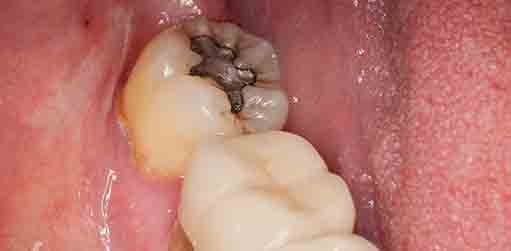

Calzas Dentales Grises

Las calzas dentales grises son una variante menos común y generalmente están asociadas con restauraciones dentales más antiguas. Hoy en día, se prefieren las calzas dentales de colores naturales para una apariencia más estética.